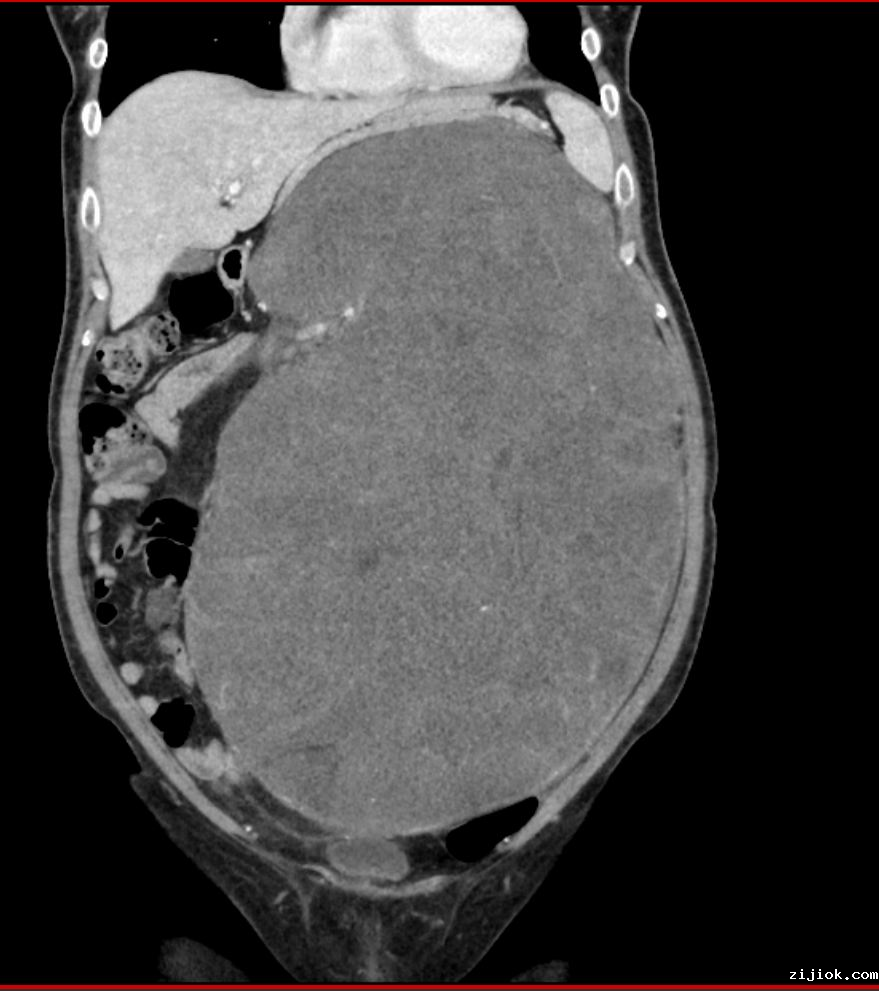

2022年以来,李女士无意间发现自己的肚子日渐增大,但日常生活中又没有任何不适,粗心的她还以为自己长胖了,直到肚子大到实在受不了,才到附四院就诊。通过增强CT、核磁共振等各项检查后,发现李女士的腹部有巨大包块,质地坚硬,不能推动,左侧上腹部盆腔区出现巨大占位性病变。

由于肿瘤巨大,已出现包绕左肾及左肾血管,比邻腹主动脉,肠系膜上动静脉,腹腔动脉、髂动静脉,脾动静脉等重要血管及腹膜后神经组织的情况,必须在避免肿瘤破损的前提下完整切除肿瘤,才能取得良好疗效,降低复发风险。

手术过程比术前预计的更加艰险,肿瘤占据了腹腔大部分空间,粘连并压迫周围脏器,肠管被严重挤压,并且肿瘤紧贴腹腔多条重要血管,手术中稍有不慎就会导致大出血危及患者生命。

姚金科仔细地将肿瘤与周围组织之间粘连一点点分离,结扎切断左肾血管。经过长达5个小时的奋战,深埋在李女士腹膜后的重磅“炸弹”终于被完整切除。切除的肿瘤大小约38×25厘米,重量达14公斤,如此巨大的肿瘤,连李女士本人也为之惊讶。